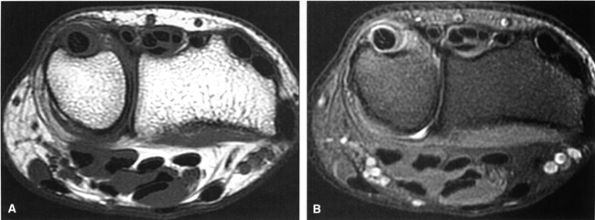

FIGURE 10.15 ● EXTENSOR CARPI ULNARIS The extensor carpi ulnaris tendon extends and adducts the wrist. It is commonly affected in tendinosis and tenosynovitis as it passes through the groove on the distal ulna. Subluxation of the extensor carpi ulnaris can also occur at this location related to disruption or insufficiency of the ligament that covers the tendon in this groove. The extensor carpi ulnaris tendon subsheath is a component of the triangular fibrocartilage complex.

|